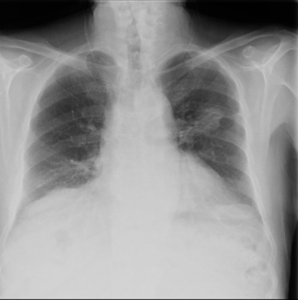

Rx PA de tórax